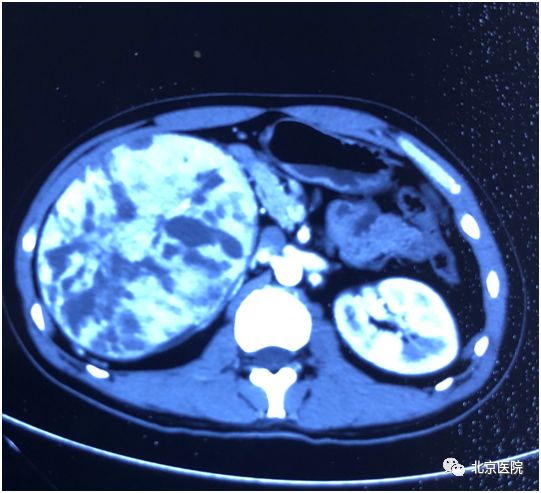

肾细胞癌是泌尿系统最常见的肿瘤之一,约占肾脏恶性肿瘤的80%-90%。近日,北京医院泌尿外科收治一名年轻男性患者,两周前自行摸到其右侧腹部有一包块,无疼痛感。遂到医院检查B超提示:右肾占位,进一步CT增强扫描提示右肾巨大占位,最大径约18cm,体积为正常肾脏8倍之大,考虑恶性,全身评估未见转移病灶,需手术根治切除治疗。但因肿瘤巨大侵犯肾脏包膜,与周围脂肪组织黏连,且肿瘤血供丰富,表面多发迂曲小静脉、质脆,术中不易剥离,容易引发大出血,增加了手术难度和风险。

术前CT显示肾脏肿瘤态势